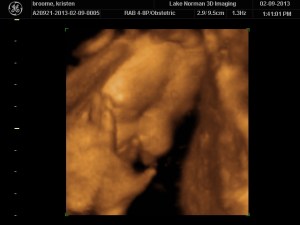

..We meet again, little boy!